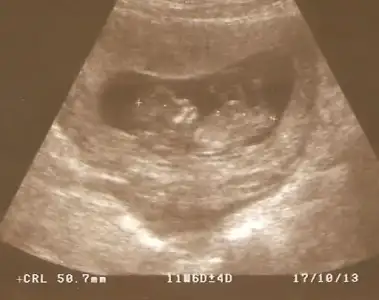

dr soylemeden siz gorun genital nub teorisi ( bebegin cinsiyeti)

anlayan arkadaşlar sizce nub belli mi cinsiyet konusunda bir fikriniz var mı?

11.haftada dr. cinsiyetine önce kız dedi, sonra pipi gördüm dedi, sonra da kordon olabilir dedi, yani bilemedi, orkidem kız demişti. 16.haftada başka bir dr. %98 kız dedi.